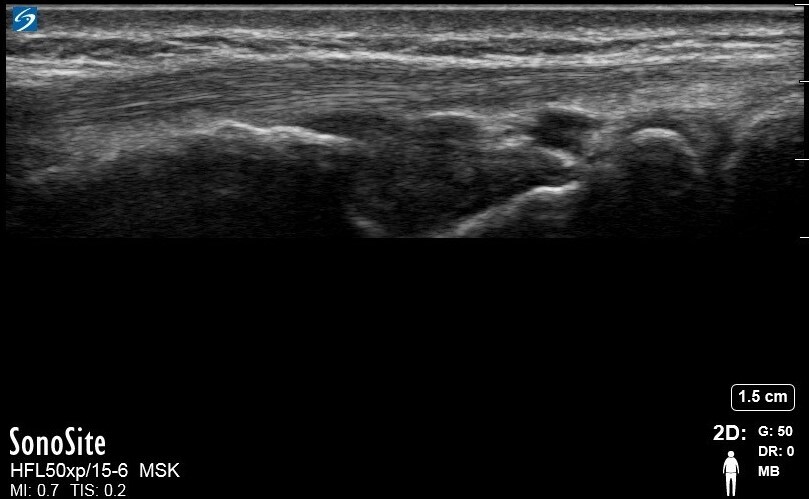

Wrist Abductor Pollicis Longus and Extensor Pollicis Brevis 2 Image